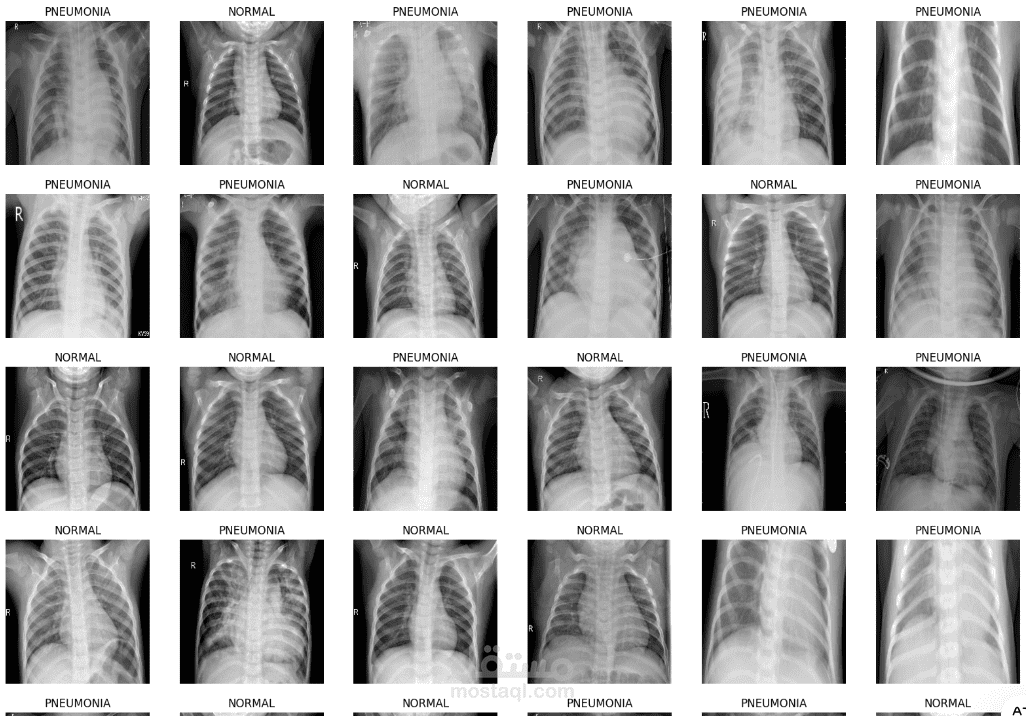

تم تصميم نموذج يعتمد على الشبكات العصبية التلافيفية (CNNs) لتصنيف صور الأشعة السينية للصدر إلى فئتين: طبيعي (Normal) والتهاب رئوي (Pneumonia). يهدف المشروع إلى دعم التشخيص الطبي باستخدام تقنيات الذكاء الاصطناعي، حيث حقق النموذج دقة اختبار بلغت 87.66%.

تم تصميم شبكة عصبية تلافيفية (CNN) مخصصة لمعالجة صور الأشعة السينية.

تم استخدام تقنيات Data Augmentation (مثل التدوير، التغيير في السطوع، الانعكاس) لتحسين التعميم وتقليل الإفراط في التدريب.

معالجة مشكلة عدم توازن الفئات باستخدام Oversampling لتجنب تحيز النموذج نحو الفئة الأكثر تمثيلًا.

دقة اختبار: 87.66%